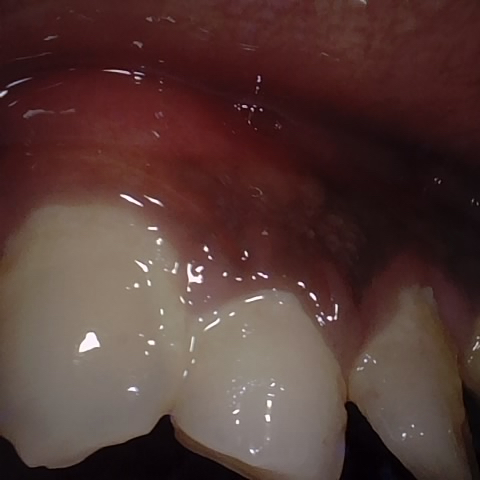

Annotated as "Good"